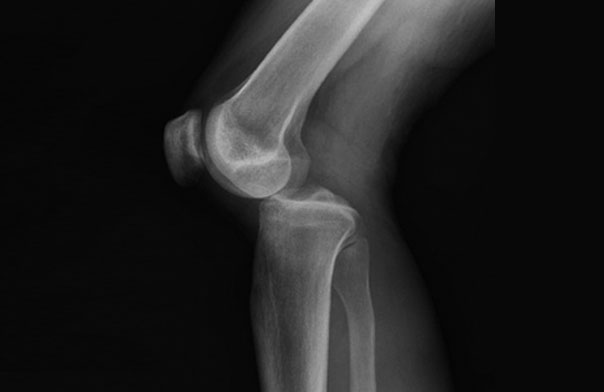

Complexe knie instabiliteiten worden veroorzaakt door trauma’s waarbij twee, drie of alle vier de ligamenten (banden) in de knie tegelijkertijd scheuren, soms in combinatie met vaat- en of zenuwletsel. Als twee of drie of zelfs alle vier van de ligamenten worden beschadigd, wordt de blessure zeer veel moeilijker te behandelen. Dit complexe knieletsel wordt een multiligamentair knieletsel of knie luxatie genoemd.